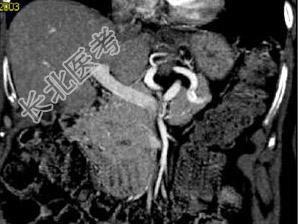

- 单项选择题根据所提供的图像,最可能的诊断是 ( )

A、胰腺癌

B、胰岛细胞瘤

C、病理性脾动脉硬化

D、假性囊肿

E、以上都不是